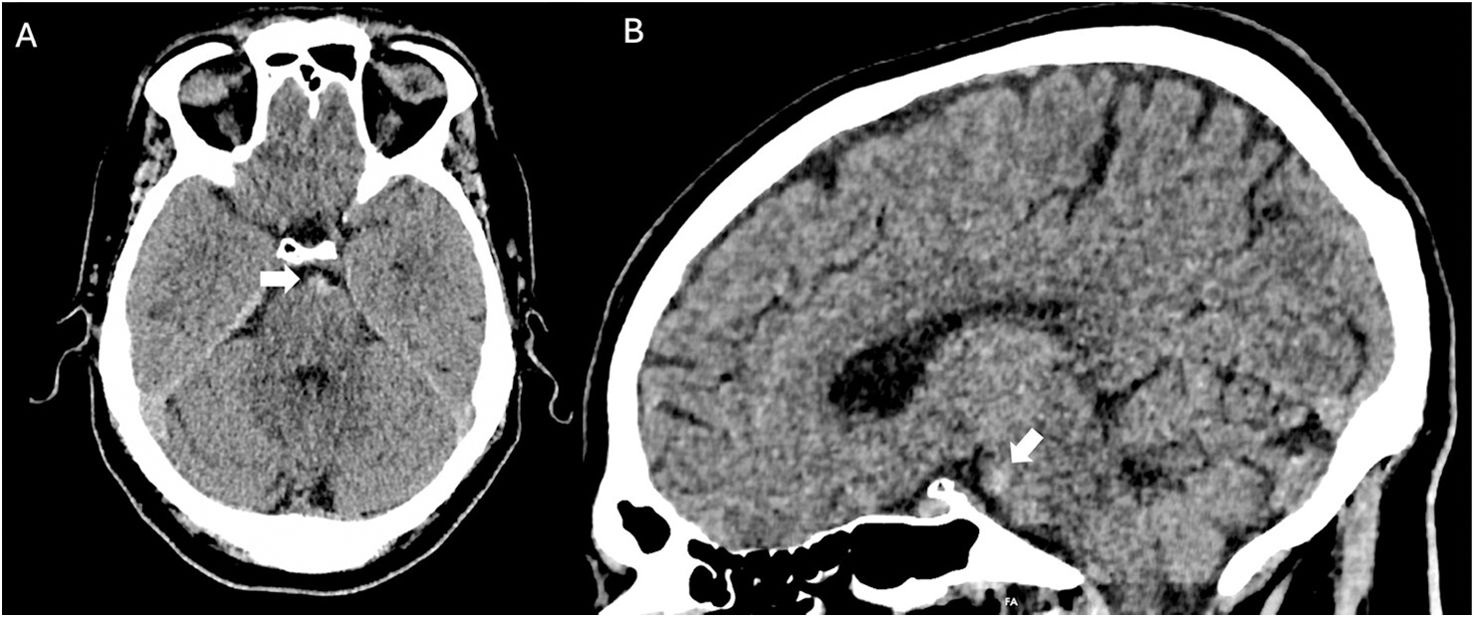

Spontaneous subarachnoid haemorrhage (SAH) is a neurological emergency that predominantly affects young adults, with a high mortality rate and severe neurological sequelae in survivors. Its most characteristic clinical manifestation is a sudden thunderclap headache, often described as the worst headache of one's life, and frequently accompanied by altered levels of consciousness and neck stiffness. Non-contrast cranial computed tomography (NCCT) is the initial diagnostic tool of choice due to its high sensitivity. Recognising the distribution patterns of haemorrhage on NCCT helps guide the aetiological diagnosis and assess the presence of complications such as hydrocephalus, intraventricular haemorrhage or cerebral oedema. This article offers a practical and detailed imaging-based guide for radiologists in the hyperacute phase of spontaneous SAH, distinguishing between aneurysmal, perimesencephalic and cortical patterns, and discusses their clinical, diagnostic and therapeutic implications.